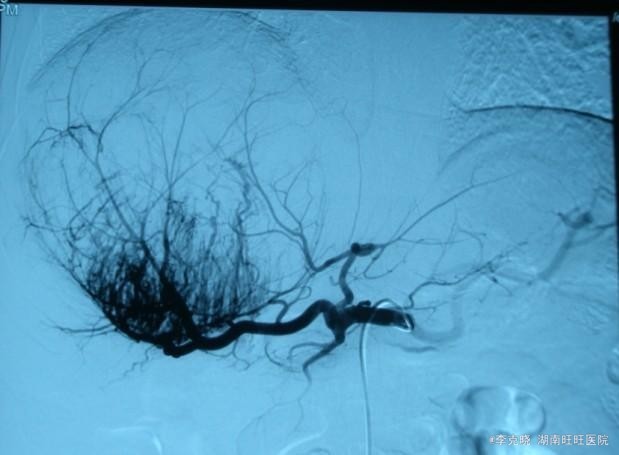

四测正常,皮肤巩膜无黄染,心肺部听诊未闻及杂音。腹平坦,未见胃肠型及蠕动波,无腹壁静脉曲张,全腹柔软,右侧肋缘深压痛,无反跳痛,肝肾无叩痛,肝肺浊音界清晰,肠鸣音正常。四肢活动自如,无水肿。 辅助检查提示:血常规、凝血常规基本正常,谷丙转氨酶278u/l,谷草转氨酶326u/l,AFP大于20000。上腹部CT增强提示:右肝巨大占位,平扫期呈低密度,动脉扫描时强化明显,静脉延迟象呈现低密度,结合病史考虑原发性肝癌可能,建议结合临床。

诊断:原发性肝癌(右肝巨块型)。治疗:考虑到患者的经济状况,结合肿瘤的影像学特点,经与患者充分沟通“以手术治疗为主的肝癌综合治疗思路”,最终患者选择先行TACE治疗。治疗后住院9天复查肝功能,转氨酶有下降趋势时,给予患者出院。一个半月后返院复查,转氨酶稍高,肿瘤内部碘油沉积满意,未见新生血管生成和新生病灶,建议患者继续观察、随访。

随访四个月,患者在第三个月时,碘油流空较多,予以加做一次TACE,碘油再次沉积良好,目前仍在随访当中。 我国是乙肝人口大国,乙肝、肝硬化、肝癌成为肝癌三步曲。无症状的乙肝病毒携带者、肝功能正常的慢性乙型、丙型肝炎,均应重视起来,不能因暂时没有症状、或者肝功能正常而不加以干预,乙肝患者一定注意DNA定量检测,若拷贝较高,建议口服抗病毒药物,如恩替卡韦,丙肝患者需定期查肝功能和影像学诊断,必要时应用干扰素等治疗,防止肝功能缓慢破坏。 肝癌的治疗从手术到多种手段的综合运用,尤其是当今手术已不存在禁区,然而中位生存时间、预后、五年生存率等20年来几乎无明显延迟。我们医务工作者是否应该认识到,对抗性的治疗是否有利于恶性疾病的治疗,扶正祛邪的祖国中医理论是否有可取之处?带瘤生存、与瘤共生和平相处是不是更由于创伤巨大的手术呢。此患者最终选择TACE,笔者认为十分赞同,经过四个月的治疗来看,肿瘤得到了有效遏制,生子速度大大延缓,而患者自身生活质量也比手术切除要高的多。